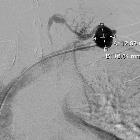

Subclavian

vein aneurysm - Case presentation and discussion. Venography of the left subclavian vein after catheterization and subsequently of the aneurysm, shows filling of the venous dilatation after the injection of contrast media, with preserved patency of the subclavian vein.

vein aneurysm - Case presentation and discussion. Venography of the left subclavian vein after catheterization and subsequently of the aneurysm, shows filling of the venous dilatation after the injection of contrast media. The dimensions of the lesion are noted.